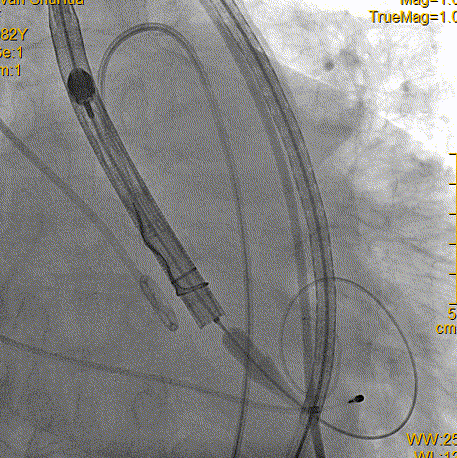

输送系统定位

瓣膜释放